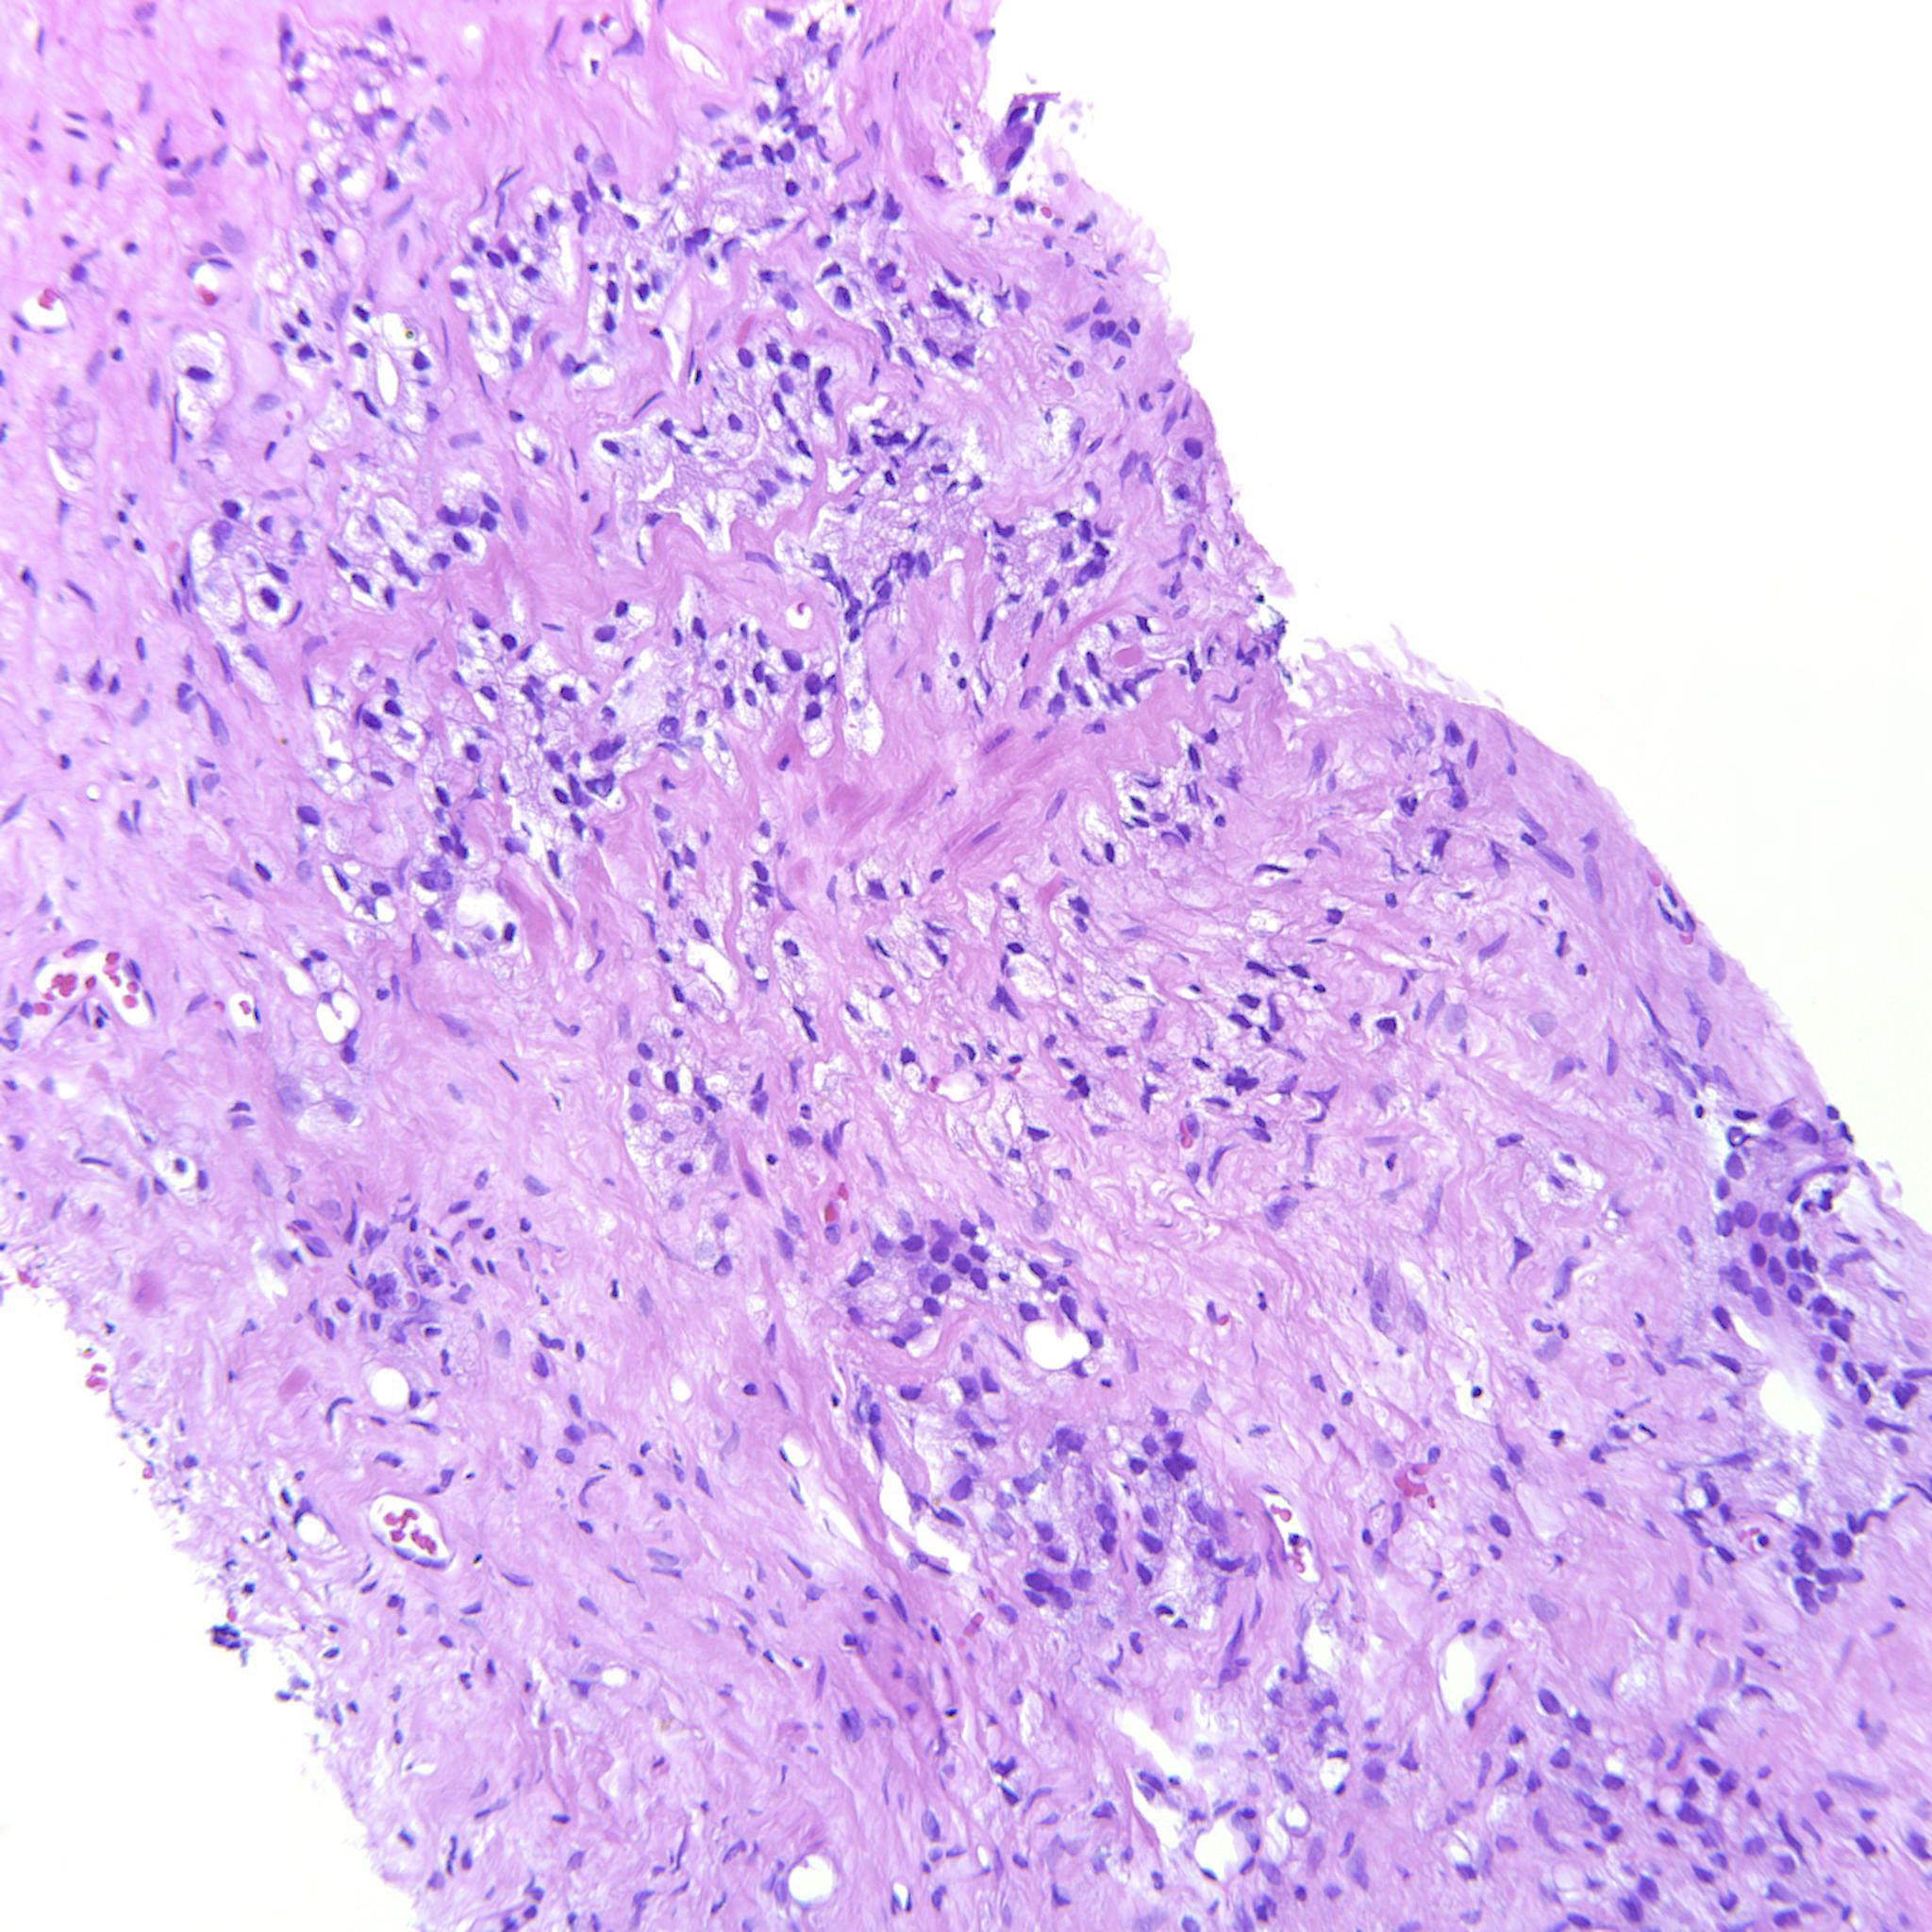

Prostate cancer grading

Case ID: 635